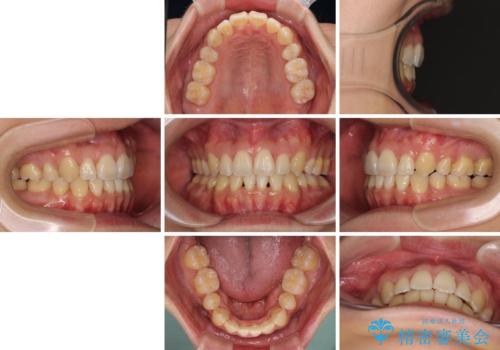

重なり合って磨きにくい前歯 ワイヤー装置での抜歯矯正

- 前歯の著しいデコボコを気にして来院された患者様です。

上顎の左右側切歯(前から2番目)が裏側に隠れいてる状態で、咬み合わせや清掃性に大きな問題が認められました。

叢生が著しいため、上下左右の小臼歯4本を抜去し、目立たないワイヤー装置にて矯正治療を行うこととしました。

下顎の歯列全体が右側にずれているため、右下のみ第二小臼歯を抜歯し、上顎は補助装置を使用して、極力上下の正中を合う位置にて咬み合わせを改善するようにしました。

元の歯列が想像できないほど、きれいな歯列に整えることができました。

第二小臼歯抜歯の矯正治療は、治療期間が長引くことが多いですが、動きが非常に良く、予定の治療期間で終えることができました。